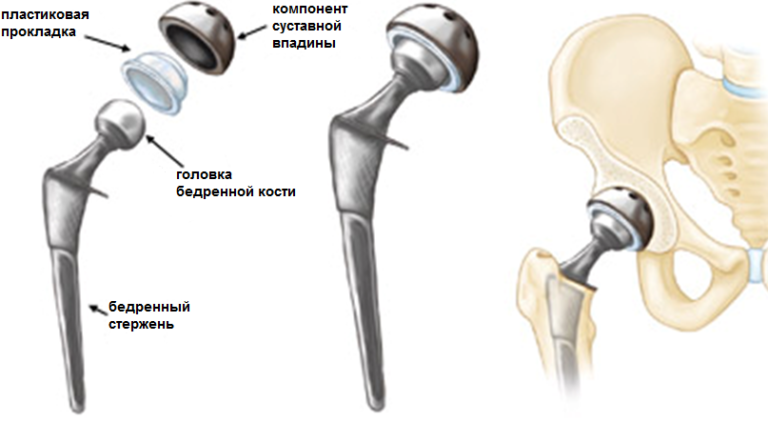

Тотальное эндопротезирование тазобедренного сустава – это операция, когда выполняют удаление поврежденной кости и хряща, с последующей заменой на протез, как головки бедренной кости, так и вертлужной впадины.

Современные разработки в области эндопротезирования направлены на увеличение срока функционирования протезов, особенно у пациентов молодого возраста, что достигается применением современных материалов в производстве протезов.

Существуют две разновидности имплантов для эндопротезирования тазобедренного сустава – бесцементные и цементные. В этой статье хотелось бы вкратце рассказать о бесцементных видах эндопротезов, в чем из преимущества и каким пациентам они показаны. Про цементное эндопротезирование читайте в статье ЭНДОПРОТЕЗИРОВАНИЕ ТАЗОБЕДРЕННОГО СУСТАВА. ЧАСТЬ 2 — ЦЕМЕНТНЫЙ СУСТАВ.

Протезы с «бесцементным» типом фиксации покрыты специальным пористым материалом, который позволяет костной ткани пациента по прошествии определенного времени врастать в эти микроскопические поры. Во время операции компоненты эндопротеза – вертлужный компонент (чашка) и бедренный компонент (ножка) впрессовываются в кость для первичной фиксации протеза. Далее, через определенный промежуток времени, костные клетки проникают в специальное пористое покрытие компонентов эндопротеза (кость — это тоже живая ткань), что обеспечивает отличную фиксацию эндопротеза в кости пациента без применения каких-либо дополнительных материалов (без костного цемента).